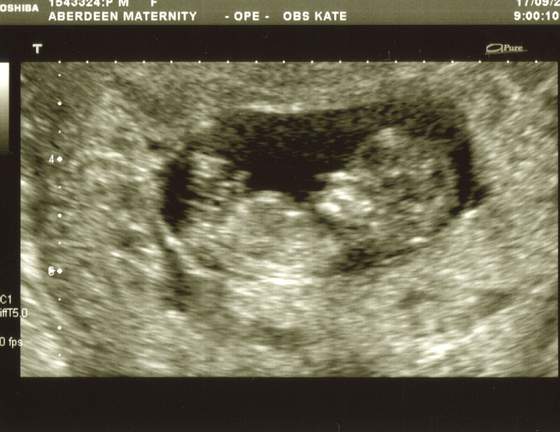

wszystko jest w najlepszym porzadku dzidzia rosnie ma 5 cm... serduszko bije jak szalone - dla mamusi![]()

No doczytałam właśnie :-) super naprawde ciesze sie razem z Toba :*nie dali Ci zadnej fotki???:-(